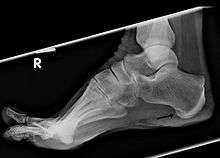

Osteophytes, commonly referred to as bone spurs[1] are bony projections that form along joint margins.[2] They should not be confused with enthesophytes, which are bony projections that form at the attachment of a tendon or ligament.[3]

Osteophytes form because of the increase in a damaged joint's surface area. This is most common from the onset of arthritis. Osteophytes usually limit joint movement and typically cause pain.[1]

Spurs can also appear on the feet, either along toes or the heel, as well as on the hands. In extreme cases, bone spurs have grown along a person's entire skeletal structure: along the knees, hips, shoulders, ribs, arms and ankles. Such cases are only exhibited with multiple exostoses.